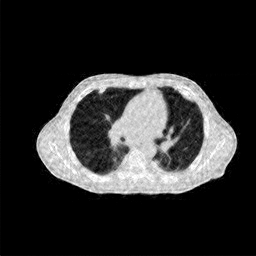

4.3 Few-View CT Reconstruction

In this section, the reconstruction performance of our proposed framework under few-view conditions will be tested. For the parallel-beam and fan-beam geometry, the number of views increases from to , uniformly distributing from to and to respectively. Such settings provide a complete benchmark of reconstruction performance, ranging from extremely sparse to relatively complete, full-view CT reconstruction. The experiment results are shown in Fig.5. Additionally, the ground truth, few-view ( views), and full-view ( views) CT reconstruction results of different methods are shown in the first and third rows of Fig.7 (parallel-beam, LIDC-IDRI dataset), and Fig.8 (fan-beam, LIDC-IDRI dataset).

4.4 Limited-Angle CT Reconstruction

To test the proposed framework’s performance on limited-angle reconstruction, we redo the experiment in the above section with the angular range changing from to for parallel-beam geometry and to for fan-beam geometry, one projection per degree. The experiment results are shown in Fig.6. Also, the ground truth and the limited-angle CT reconstruction results of different methods are shown in the row of Fig.7 (parallel-beam, LIDC-IDRI dataset), and Fig.8 (fan-beam, LIDC-IDRI dataset).

(a) Ground Truth

30.15dB

(b) ASD-POCS

39.35dB

(c) RBP-DIP

27.10dB

(d) DIP

23.88dB

(e) MED50

20.59dB

(f) RED-CNN